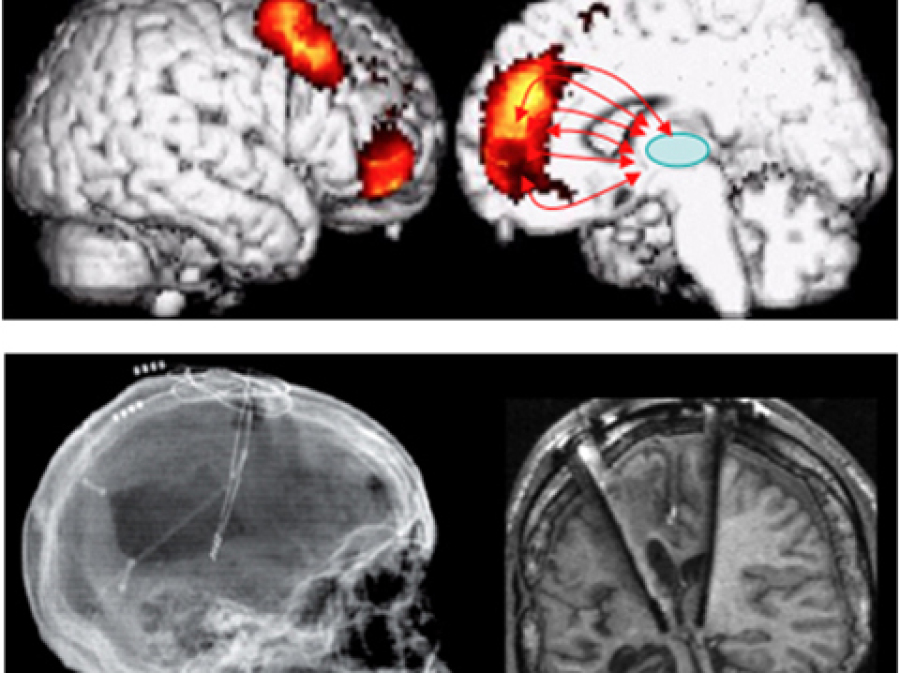

Learn MoreHead Injury Management

Head injury management, surgery, intensive care and rehabilitation